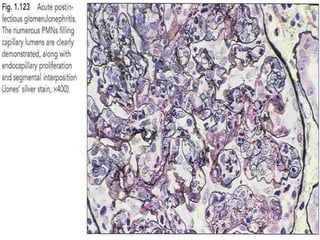

Light microscopy

 Light microscopy shows a diffuse proliferative

glomerulonephritis with prominent endocapillary

proliferation and numerous neutrophils.

• Light microscopic findings

• Early stage → glomerular hypercellularity

• Later stage → Proliferation of intrinsic

endothelial & mesangial cells